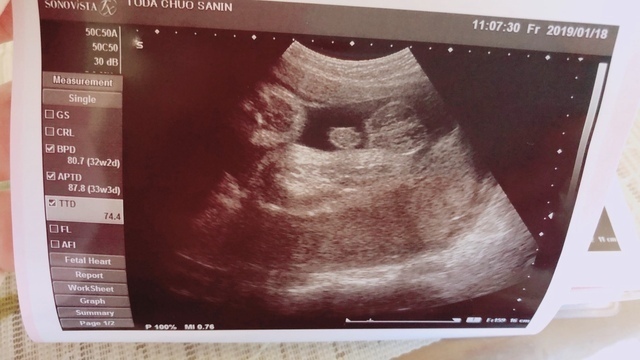

32週1日(32w1d・男の子)|mai0726 さん(31歳)

エコー写真撮影時のエピソード:

ずっと女の子と言われていたのに、年明けになってやっぱり男の子と判明。その時のエコーです。元々お腹が縦に出ていて、周りからは男の子?とよく聞かれてました。男女どちらでも元気ならいいのですが、3ヶ月近く女の子としてお腹と付き合ってきたのに。。。なんだか拍子抜けでした